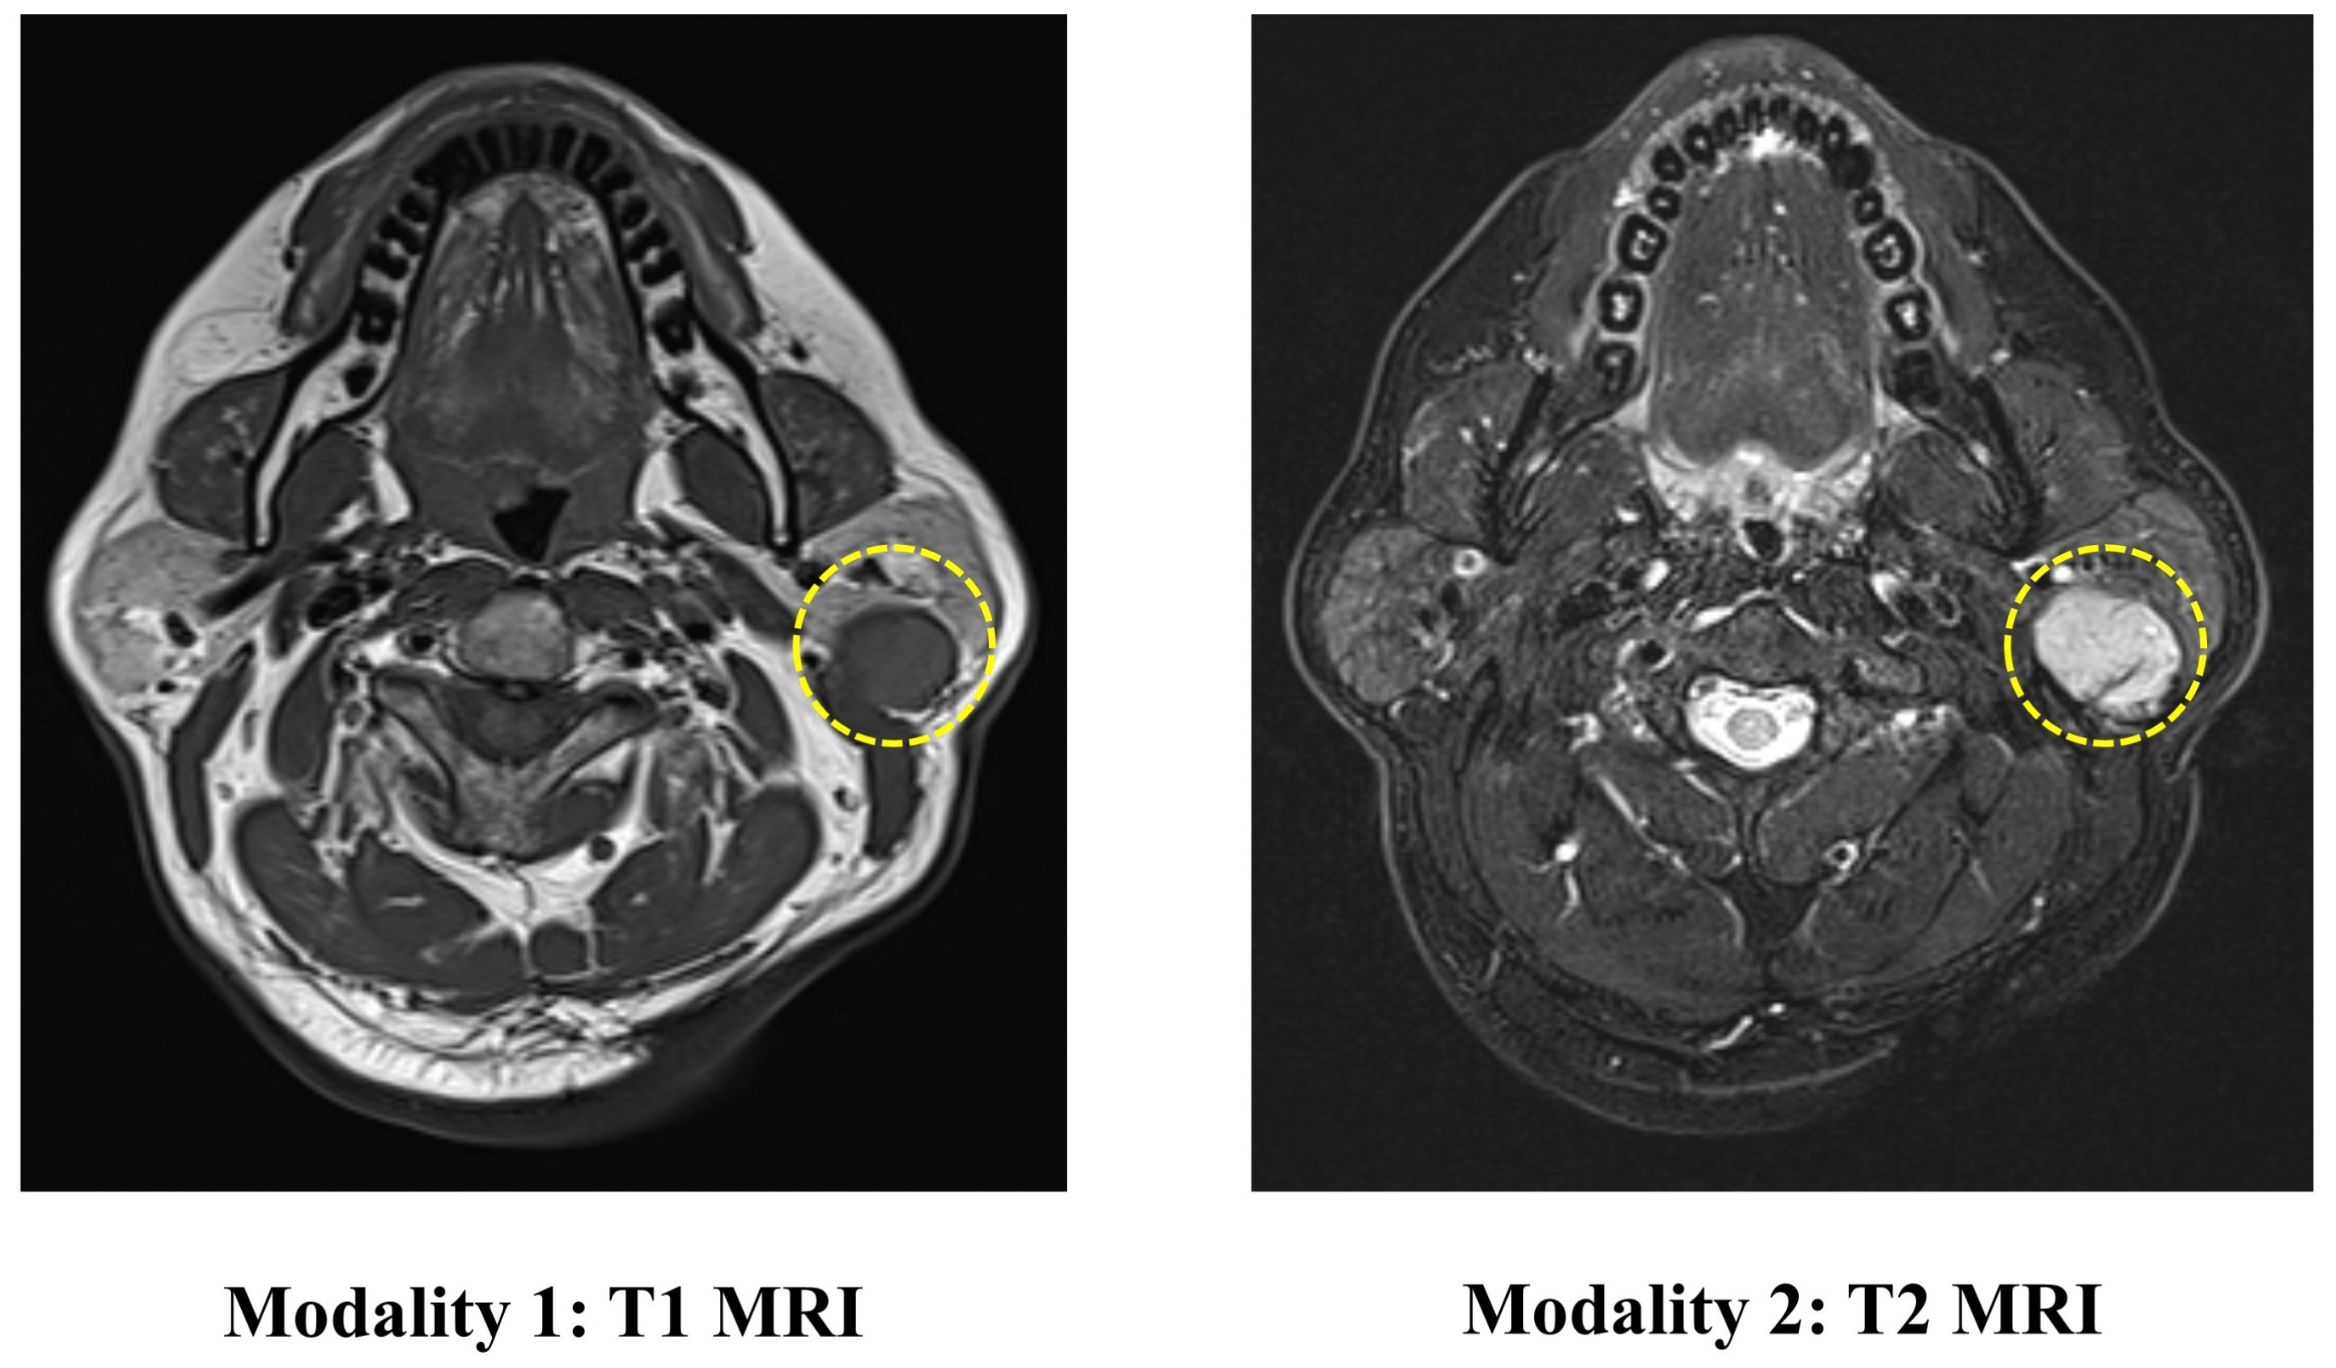

The PGT dataset contains 344 head and neck MRI examinations carried out at the Stomatological Hospital of China Medical University. The ethics board approved the use of the images for this research. This dataset includes two modalities of MRI (T1 and T2), as shown in Figure 4. The ground truth labels are obtained from biopsies.

Figure 4.

An illustration of the images in the PGT dataset. The yellow circle represents the location of the tumor.